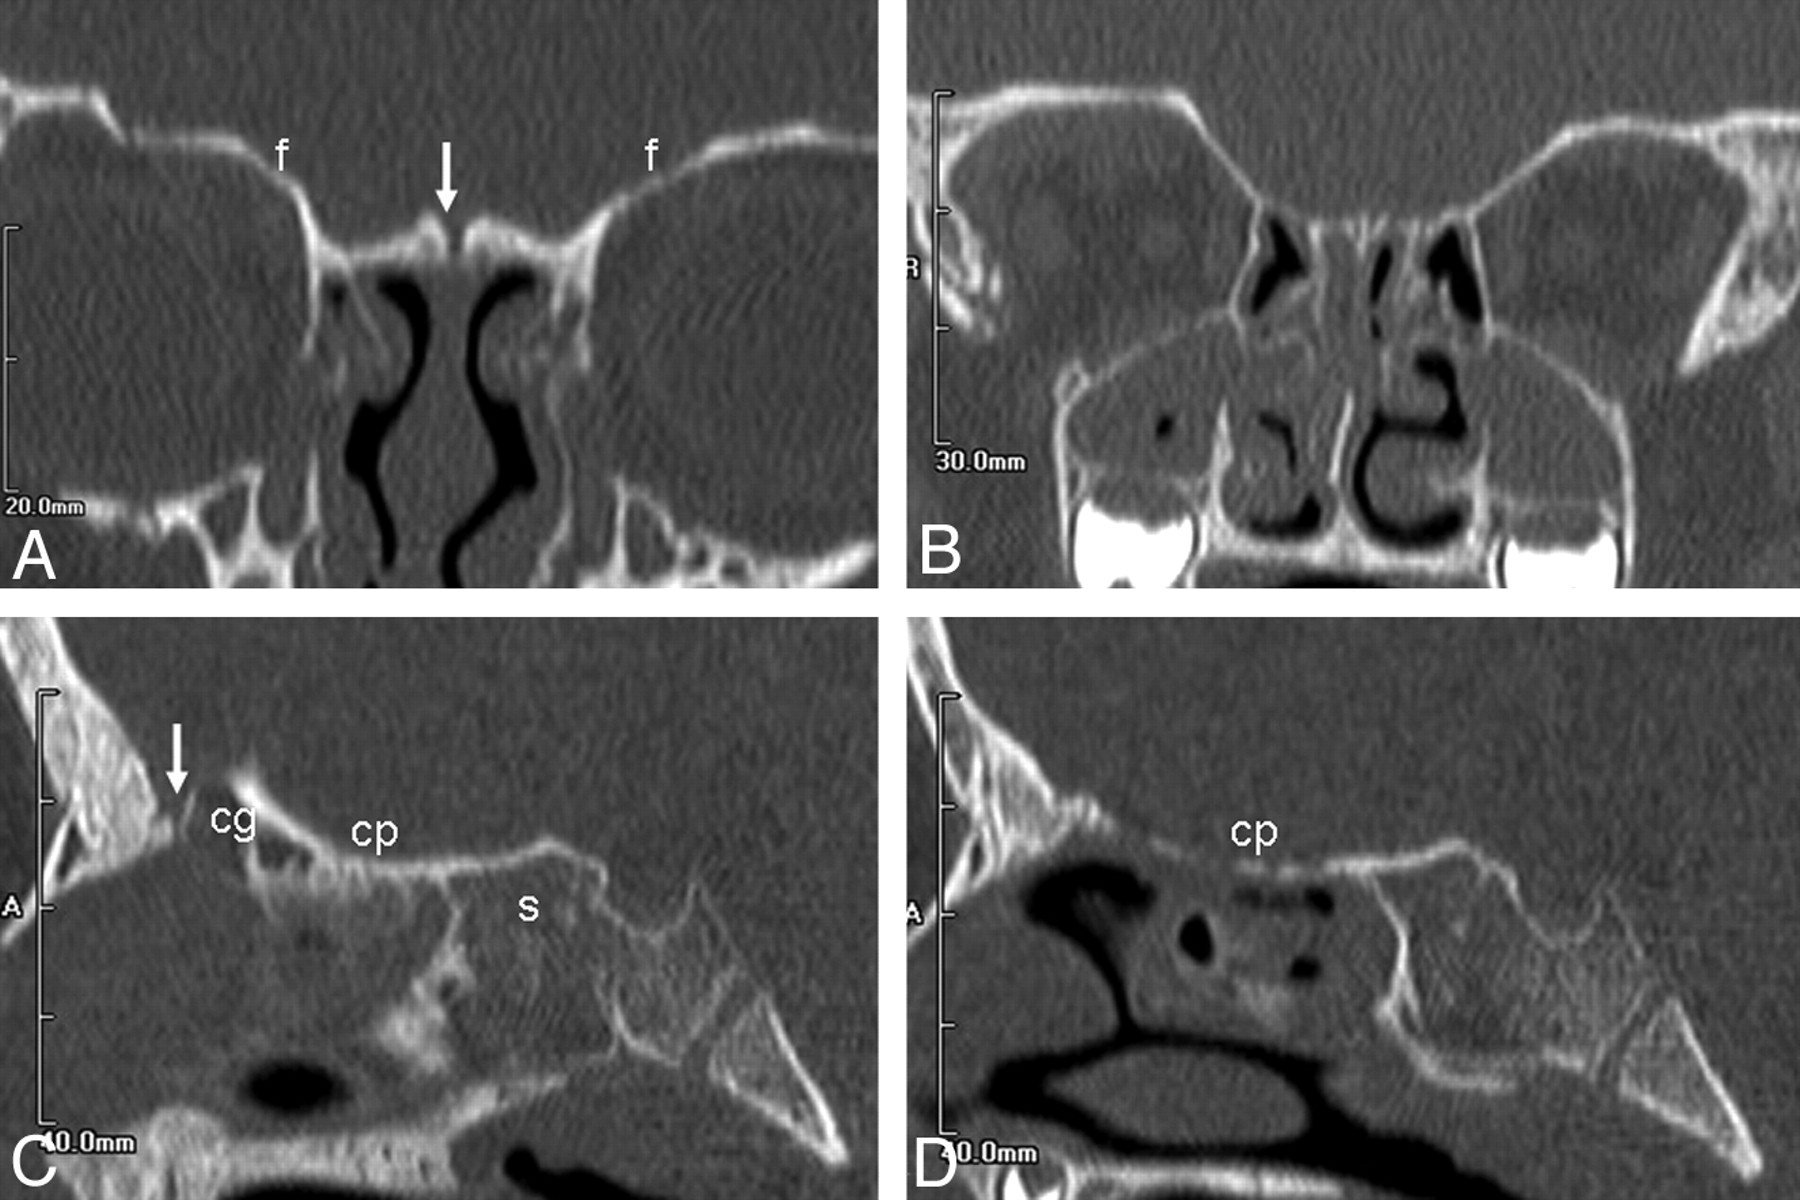

Age, 22 days. Anterior (A) and posterior (B) coronal, midline (C), and parasagittal (D) images show ossification of the frontal bones and superior turbinates (asterisks) but no ossification of the cribriform plate or crista galli (arrows).

Age, 3 years 3 months. Anterior (A) and posterior (B) coronal, midline (C), and parasagittal (D) images show progressive ossification of the cribriform plate posteriorly, with only a small persistent unossified portion of the skull base anteriorly (arrow).